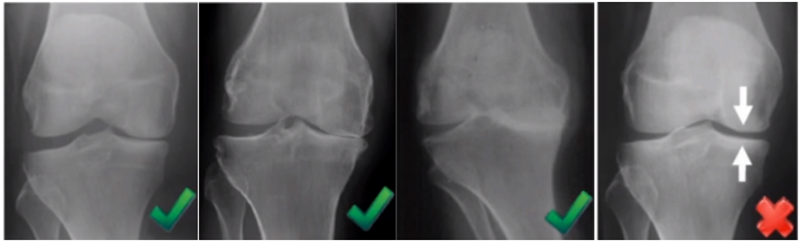

二、单髁置换的适应证——外翻应力片

屈曲20°外翻应力:看外侧软骨

外翻应力片可以辅助评价外侧间室关节软骨厚度是否正常,以及内侧副韧带功能是否完整。外侧全层软骨、外侧有骨赘的情况下都不是禁忌证,如外侧出现软骨磨损则为禁忌证。

外翻应力片还可以观察内侧间隙,如内侧副韧带出现挛缩,间隙狭窄,那么此时不适合单髁。

检查时注意X线的投照角度要平行于关节线方向,以保证准确。

可以矫正畸形,恢复关节间隙和MCL张力